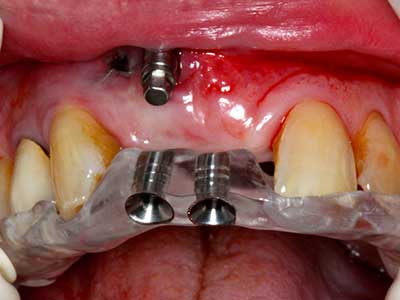

Para la extracción de implantes es posible realizar la preparación de una tapa ósea vestibular que, tras retirar el tornillo del implante, vuelve a fijarse y, de este modo, mantiene el contorno de la apófisis alveolar.